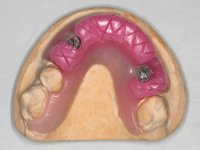

Inicialmente foram confecionadas duas novas próteses removíveis. O dente 1.3 foi extraído quando da colocação das próteses. Feito o estudo imagiológico necessário, foram colocados 4 implantes no maxilar superior. Após 3 meses de osteointegração foi feita a impressão para a confeção de ceras de articulação montadas em placa base aparafusadas aos implantes. Estas ceras foram utilizadas na recolha das relações inter-maxilares e na tentativa de proporcionar apoio ao lábio superior. Foi feita a prova de dentes com estes montados em placas base aparafusadas permitindo uma avaliação estética dinâmica muito interessante. Sendo validada esteticamente pela paciente, esta prova deu origem a uma muralha de silicone que orientou laboratorialmente a confeção da infraestrutura metálica. A infraestrutura metálica com os dentes montados em cera foi provada em boca, permitindo simultaneamente verificar a sua adaptação bem como a estética final. O trabalho final foi colocado em boca sendo acompanhado de instruções rigorosas de técnicas de higiene oral bem como da informação da necessidade de consultas de controlo periódicas.